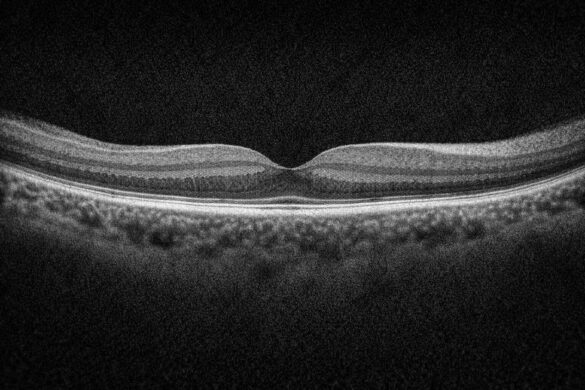

OCT(光干渉断層計)は眼科診療に欠かせない検査機器ですが、どのモデルを導入すべきか迷う方も多いのではないでしょうか。

今回は、日本国内で導入例が多い ニデック社のRS-330 と、グローバルスタンダード機 ZEISS社のCIRRUS を徹底比較して、それぞれの特徴や性能差についてまとめます。

| 画像鮮明度 | ◎ 非常に高精細 | ○ 標準(デノイジングで対応) |